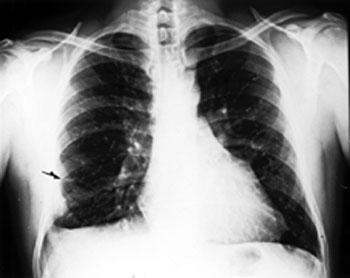

Embolia pulmonar

Al igual que ocurre en la TVP, el diagnóstico de certeza del embolismo pulmonar (EP) precisa de exploraciones complementarias, ya que las manifestaciones clínicas son frecuentes pero muy poco específicas. Los signos y síntomas más frecuentes son disnea, dolor pleurítico y taquipnea. Pero una vez se han hecho todas las pruebas pertinentes y se ha diagnosticado una embolia pulmonar deberemos tratarla para ello el tratamiento varia según la fase en que esté la embolia, vamos a ver el tratamiento para la fase crónica.